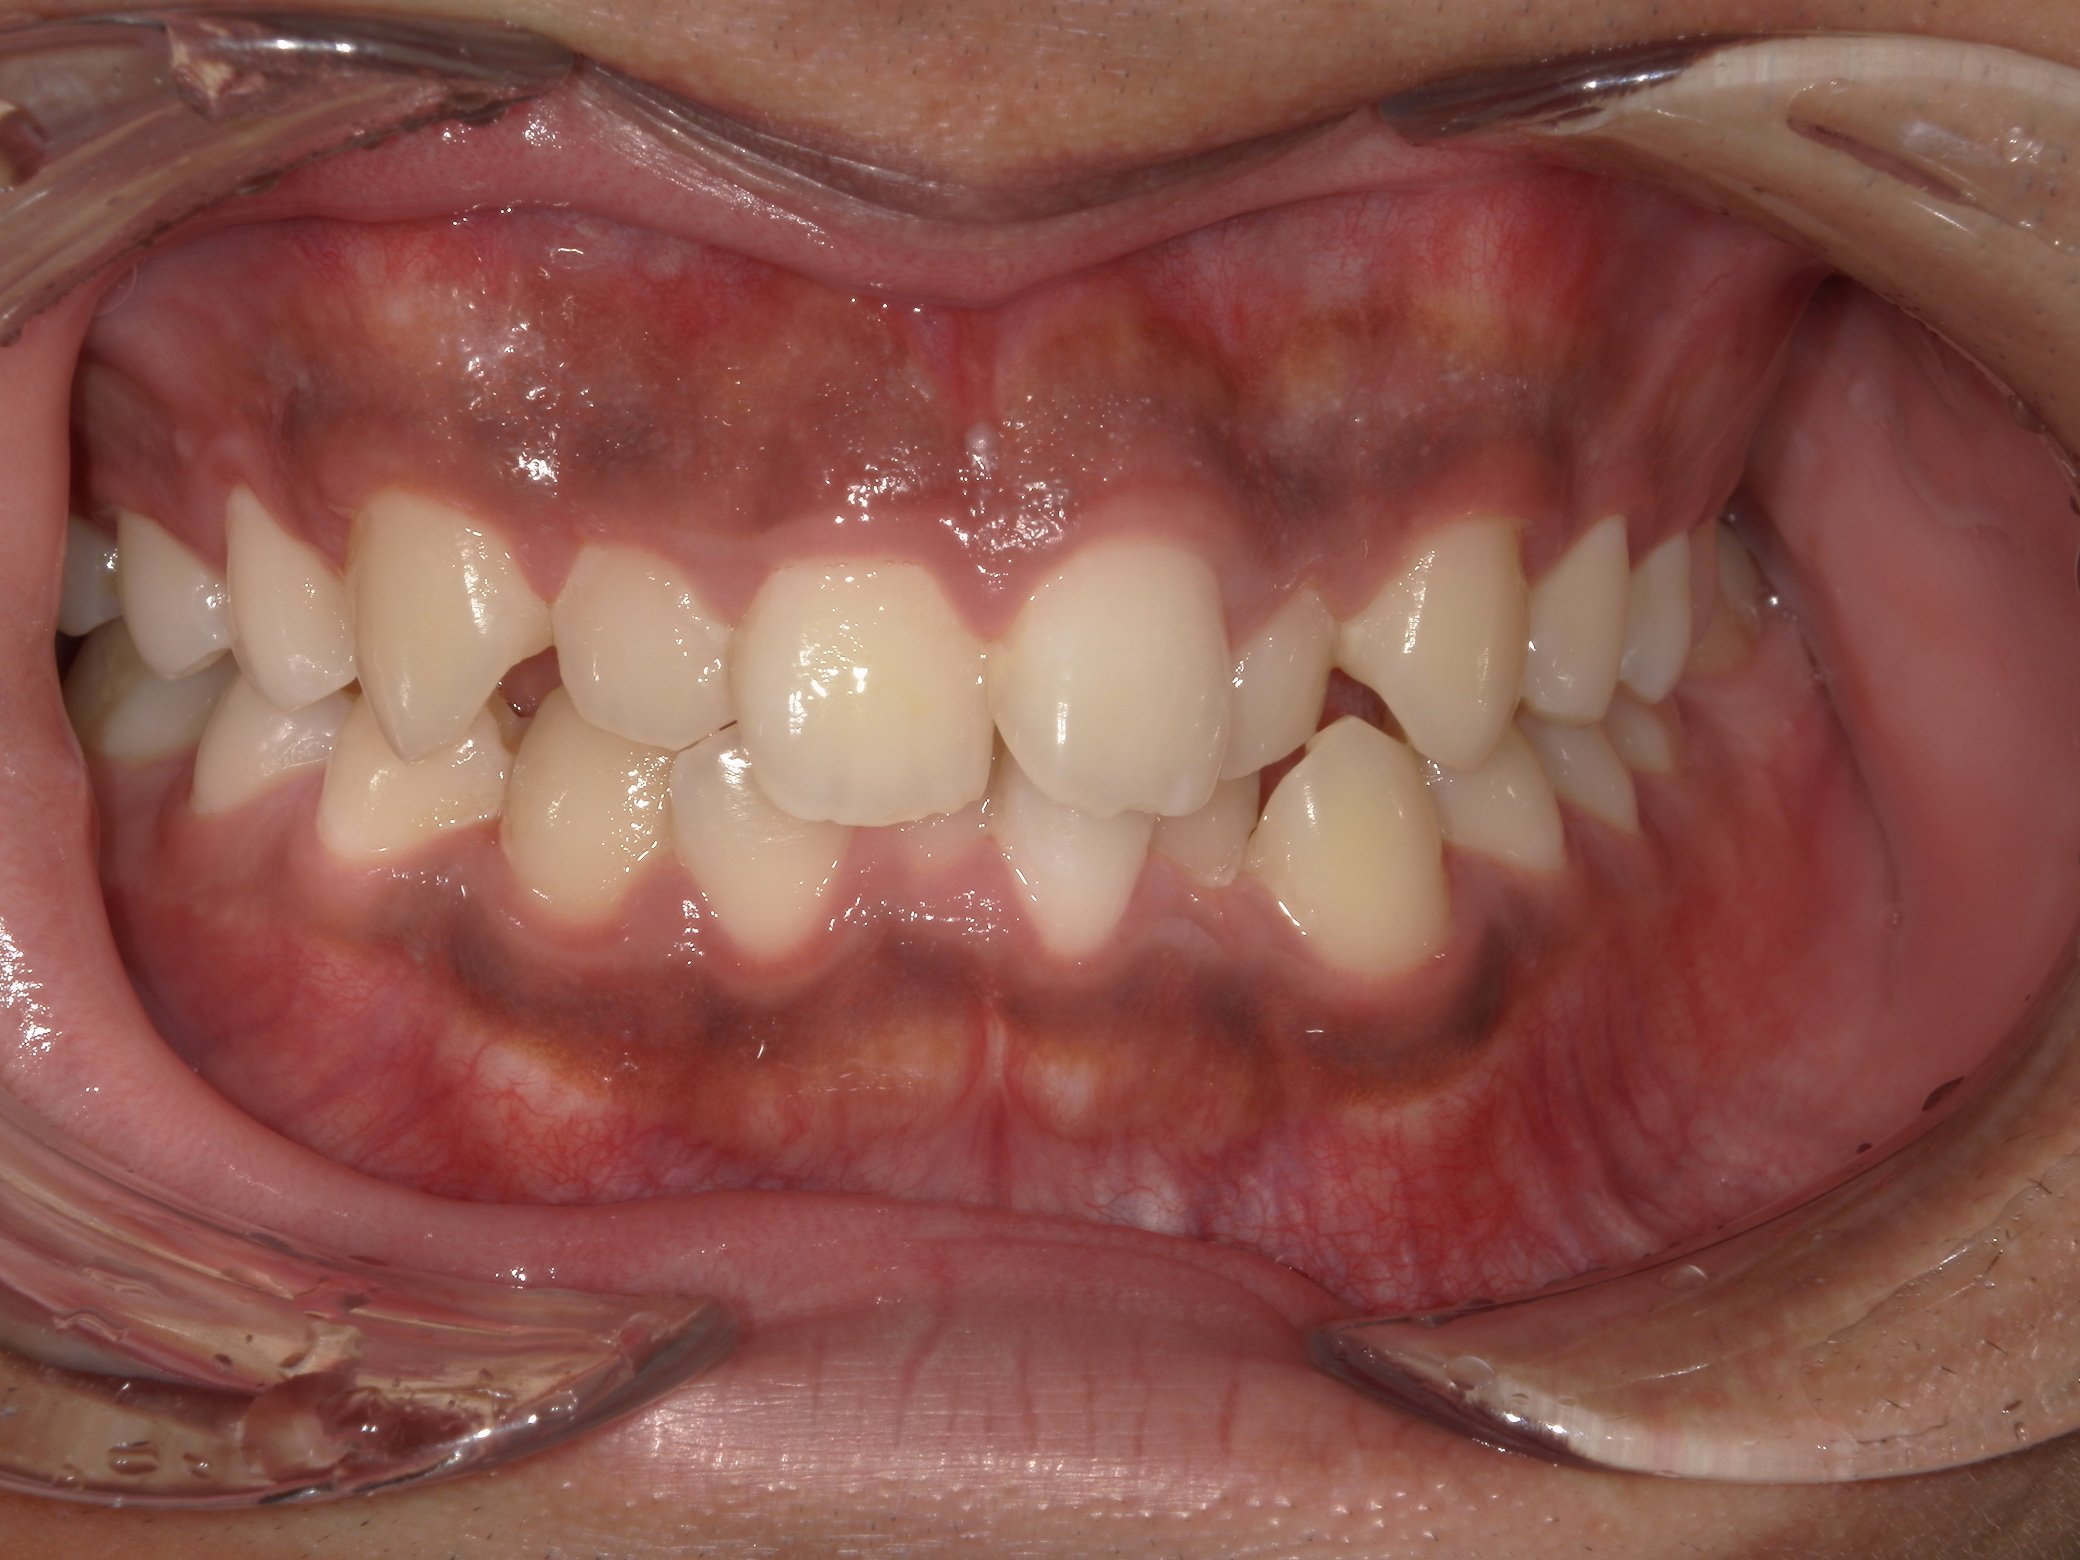

After

(治療後)

患者様情報 23歳 女性 診断名 上顎前突、叢生(そうせい) 治療内容 マウスピース矯正(クリアコレクト) 期間・通院回数 約18か月 / 20回 費用(総額) 857,000円(税込) リスク・副作用 治療の初期段階では痛みや不快感が生じやすくなりますが、通常1週間前後で慣れていきます。 マウスピース矯正の症例 2